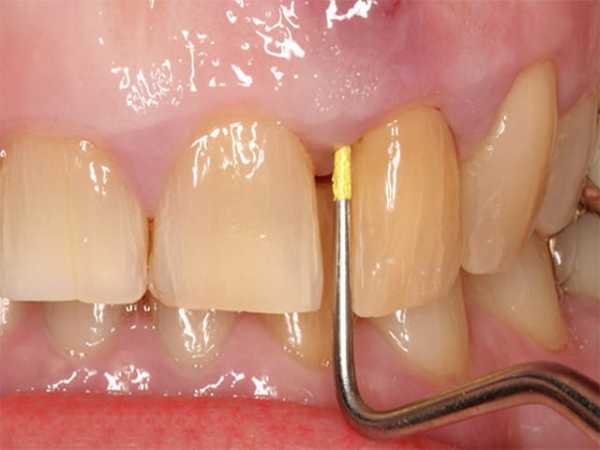

На ранних стадиях, когда гнойник еще зреет, есть возможность сохранить зуб. Для этого необходимо обеспечить отток некротических масс. Врач под местной анестезией разрезает десну, чтобы получить доступ к надкостнице. Затем промывает полость антисептиками и устанавливает дренаж. В некоторых случаях просверливают пораженные твердые ткани и прочищают корневые каналы.

Врач, используют анестезию, чистит десна и костную ткань. Если при обращении к стоматологу флюс уже прорвал, то врач делает разрез десны и вычищает гнойные массы.

Если нарыв еще не вскрылся, то врач устанавливает специальный дренаж, который будет выводить гной. Пораженный участок десны обрабатывается антибактериальными средствами для дезинфекции. Если зуб в запущенном состоянии, то врач удаляет его, так как он является источником бактерий. Если доктор устанавливает дренаж, то через пару дней гной выходит, доктор удаляет его и зашивает десну.

- Вскрывается рядом стоящий зуб с помощью бормашины.

- Разрезается десна и вставляется специальный резиновый дренаж, для предотвращения заживления разреза до момента выведения всего гноя.